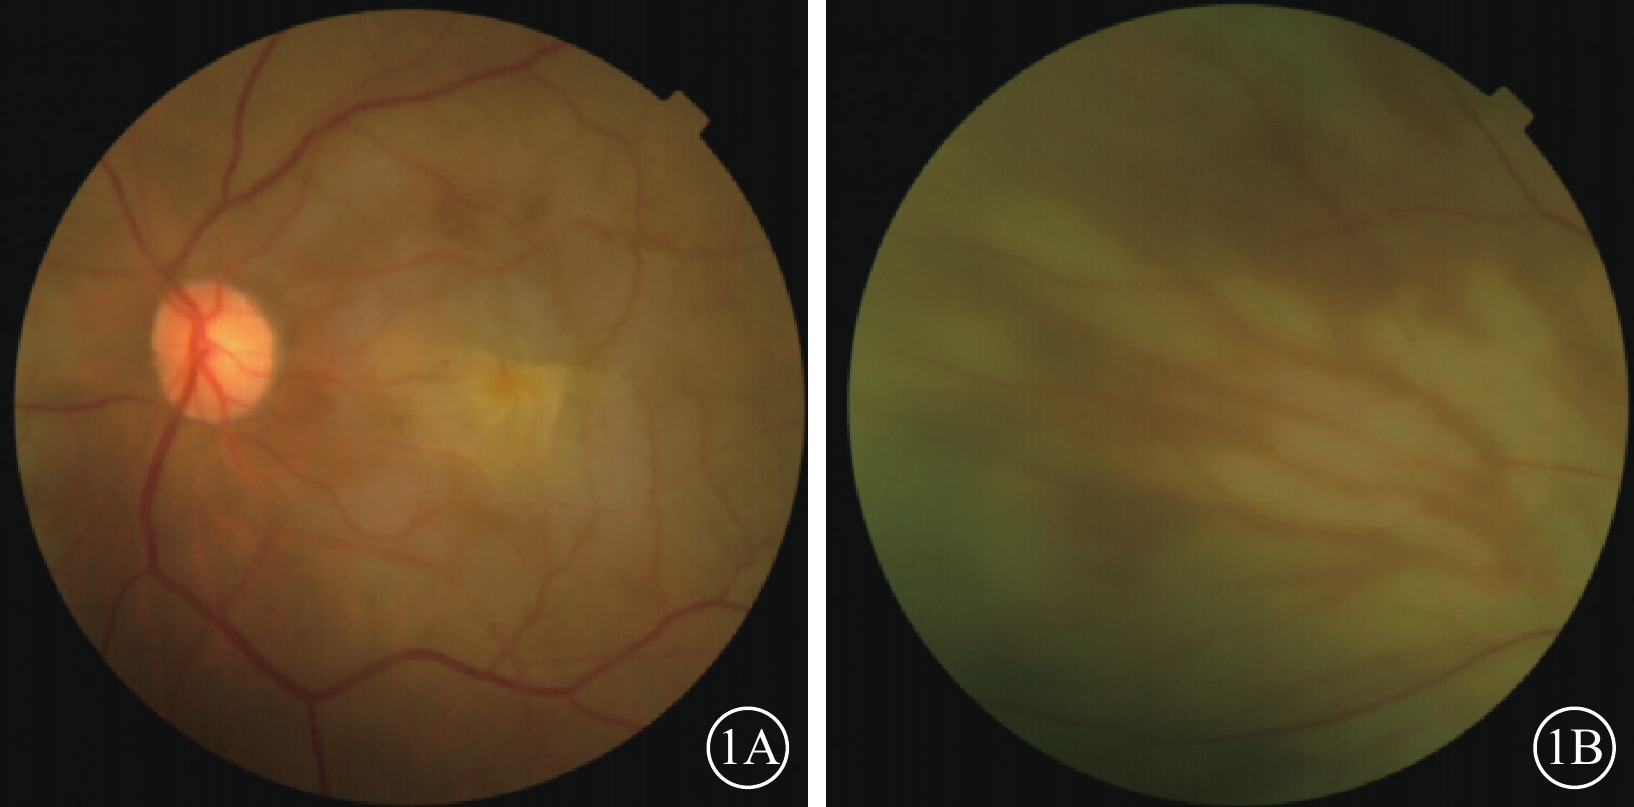

患者女,77歲。因左眼視力下降8個月加重1個月于2017年10月26日至北京大學第三醫院眼科中心就診。既往曾有晨起時一過性左眼黑矇史;否認高血壓、糖尿病等全身病史。甘油三酯輕度升高,出凝血時間正常。眼部檢查:左眼視力0.1,矯正不能提高;右眼視力0.2,矯正視力0.3。左眼眼壓(IOP)20 mmHg(1 mmHg=0.133 kPa)。晶狀體核性混濁;眼底可見黃斑前膜。右眼晶狀體混濁,其余眼前節及眼底檢查未見明顯異常。診斷:(1)左眼白內障;(2)左眼黃斑前膜。于10月28日在局部麻醉下行左眼白內障超聲乳化IOL植入、23G玻璃體切割手術(PPV)。手術參數:超聲乳化瓶高85 cm,PPV時IOP 28 mmHg。手術時間45 min,過程順利。手術后第1天,左眼視力眼前數指。角膜輕度水腫;眼底視盤邊界清楚,色澤正常,黃斑區輕度水腫。IOP 37 mmHg,給予降眼壓藥物控制。手術后第2天,患者自述晨起時左眼黑矇,檢查左眼視力上方眼前手動。眼底視盤邊界清楚,顏色淡;后極部視網膜灰白水腫,無櫻桃紅斑(圖1A),視網膜動脈內血流中斷;視盤鼻側見羽毛狀灰白水腫楔狀區域(圖1B),與視網膜血管分布不一致。IOP 18 mmHg。FFA檢查,視盤和脈絡膜充盈遲緩,視網膜中央動脈14″ 73開始充盈,可見動脈前鋒,21″17靜脈尚未完全充盈;25″92視盤鼻側開始顯現由邊界清楚羽毛狀強熒光拼成的楔形區域,隨時間延長熒光增強,但始終邊界清楚(圖2A)。次日ICGA檢查,脈絡膜充盈遲緩,至10′42″20時視盤鼻側開始出現脈絡膜強熒光區,與FFA所見形態部位一致(圖2B)。OCT檢查,視網膜內層彌漫強反射,層次不清,黃斑中心凹處呈皺褶狀隆起(圖3),鼻側病灶區脈絡膜層面異常反射不顯著。頸動脈彩色多普勒血流顯像(CDFI)檢查,雙側頸動脈硬化斑塊形成。心臟CDFI檢查,左室泵功能正常,舒張功能減低;主動脈瓣輕度關閉不全。神經內科初步診斷:頸內動脈系統短暫性腦缺血發作。頭頸部CT血管造影(CTA)檢查,雙側頸內動脈起始部血管壁混雜斑塊形成,管腔變窄。頭顱CT檢查,多發腔隙性腦梗死,軟化灶。腦白質疏松,腦萎縮。未行頭頸部數字減影血管造影。24 h橈動脈動態血壓監測結果:白天平均血壓121/60 mmHg,脈壓差60.7 mmHg;夜間平均血壓110/51 mmHg,脈壓差59.7 mmHg。最終臨床診斷:(1)左眼脈絡膜三角綜合征;(2)左眼視網膜中央動脈阻塞(CRAO);(3)左眼內低灌注。

左眼手術后第2天彩色眼底像。1A示后極部,視網膜灰白水腫,呈淡黃色皺褶狀水腫隆起;1B示視盤鼻側,可見羽毛狀灰白水腫楔狀區域

左眼手術后第2天彩色眼底像。1A示后極部,視網膜灰白水腫,呈淡黃色皺褶狀水腫隆起;1B示視盤鼻側,可見羽毛狀灰白水腫楔狀區域

圖1

左眼手術后第2天彩色眼底像。1A示后極部,視網膜灰白水腫,呈淡黃色皺褶狀水腫隆起;1B示視盤鼻側,可見羽毛狀灰白水腫楔狀區域

圖1

左眼手術后第2天彩色眼底像。1A示后極部,視網膜灰白水腫,呈淡黃色皺褶狀水腫隆起;1B示視盤鼻側,可見羽毛狀灰白水腫楔狀區域